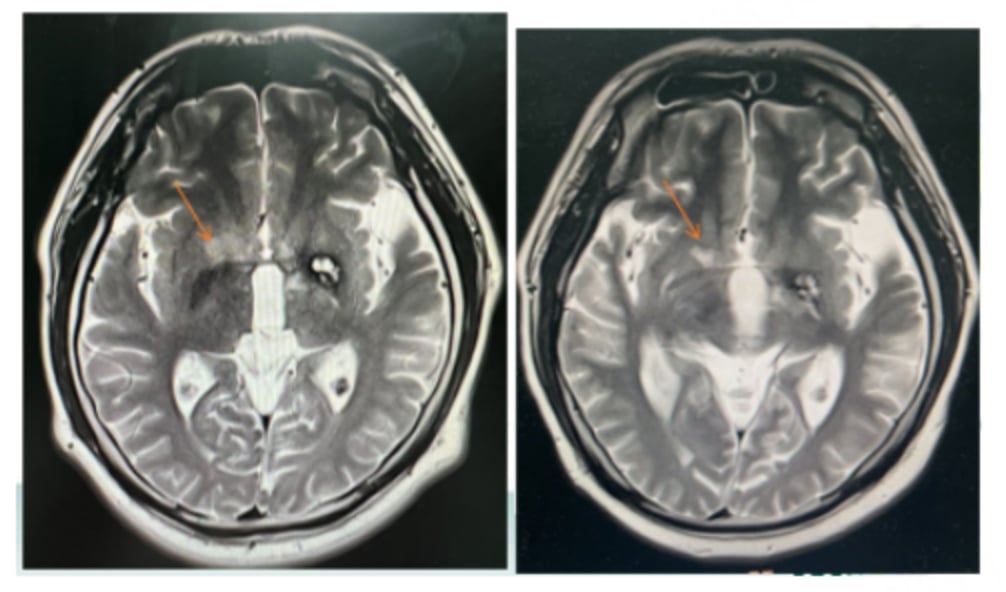

由于患者无法再次进行放疗,医疗团队决定采用以替尼泊苷为核心的联合化疗方案。具体用药包括:利妥昔单抗、替尼泊苷、异环磷酰胺、顺铂和地塞米松。经过3个疗程的治疗后,影像学评估显示患者达到了部分缓解(PR),颅内病灶明显缩小,病情得到有效控制。

尽管后续因新冠感染暂停治疗一个月,但患者病情依然稳定,显示出该方案带来的持续获益。这一成功案例表明,替尼泊苷联合化疗对于HD-MTX治疗失败的年轻患者是一种有效的挽救治疗选择。